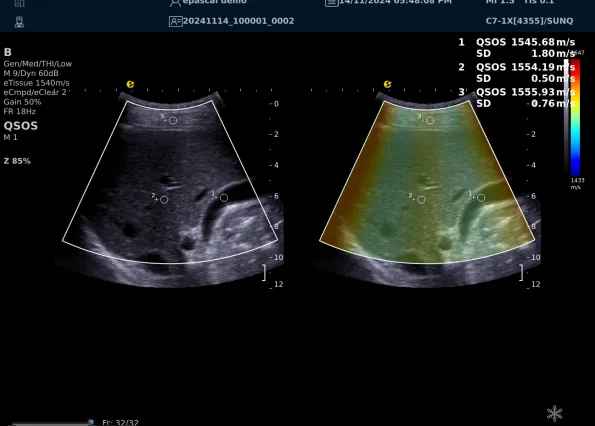

640.jpg123 (2).jpg可以设想,单位时间可发射的脉冲波越多、单位面积可发射的脉冲波越密集,得到的数据结果就越快、越多。也就是说,如果医生希望得到实时、大幅的声速定量图像,就需要超声系统具备“超快速”发射和接收的能力,3377体育医疗(ESI)ePascal东风系列超声平台的200+倍成像速度,成为了这项新技术得以临床应用的重要条件。

以上为应用声速定量成像技术检查肝脏的超声图像,图中在取样框内选择了三个测量区域,得出了各区域内的组织声速值以及声速衰减系数等结果。